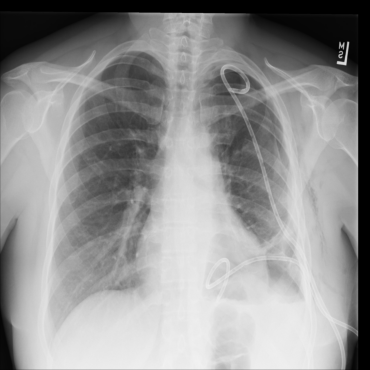

The availability of large public datasets and the increased amount of computing power have shifted the interest of the medical community to high-performance algorithms. However, little attention is paid to the quality of the data and their annotations. High performance on benchmark datasets may be reported without considering possible shortcuts or artifacts in the data, besides, models are not tested on subpopulation groups. With this work, we aim to raise awareness about shortcuts problems. We validate previous findings, and present a case study on chest X-rays using two publicly available datasets. We share annotations for a subset of pneumothorax images with drains. We conclude with general recommendations for medical image classification.